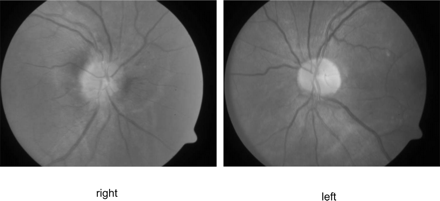

平均42岁男子,他的血压230/130毫米汞柱,面对权利brachiofacial弱点从急性左内部梗死。眼底镜检查显示严重高血压变化,盘水肿、动静脉尖酸刻薄的,和银布线,局限于右眼(图1)。视力是正常的。没有霍纳氏综合征或颈部疼痛。脖子先生扫描显示左颈内动脉严重狭窄,从起源到颅底,提示颈动脉解剖(图2)。结果血流量减少左视网膜免受严重高血压的影响。1加速高血压颈动脉解剖的可能的原因。2